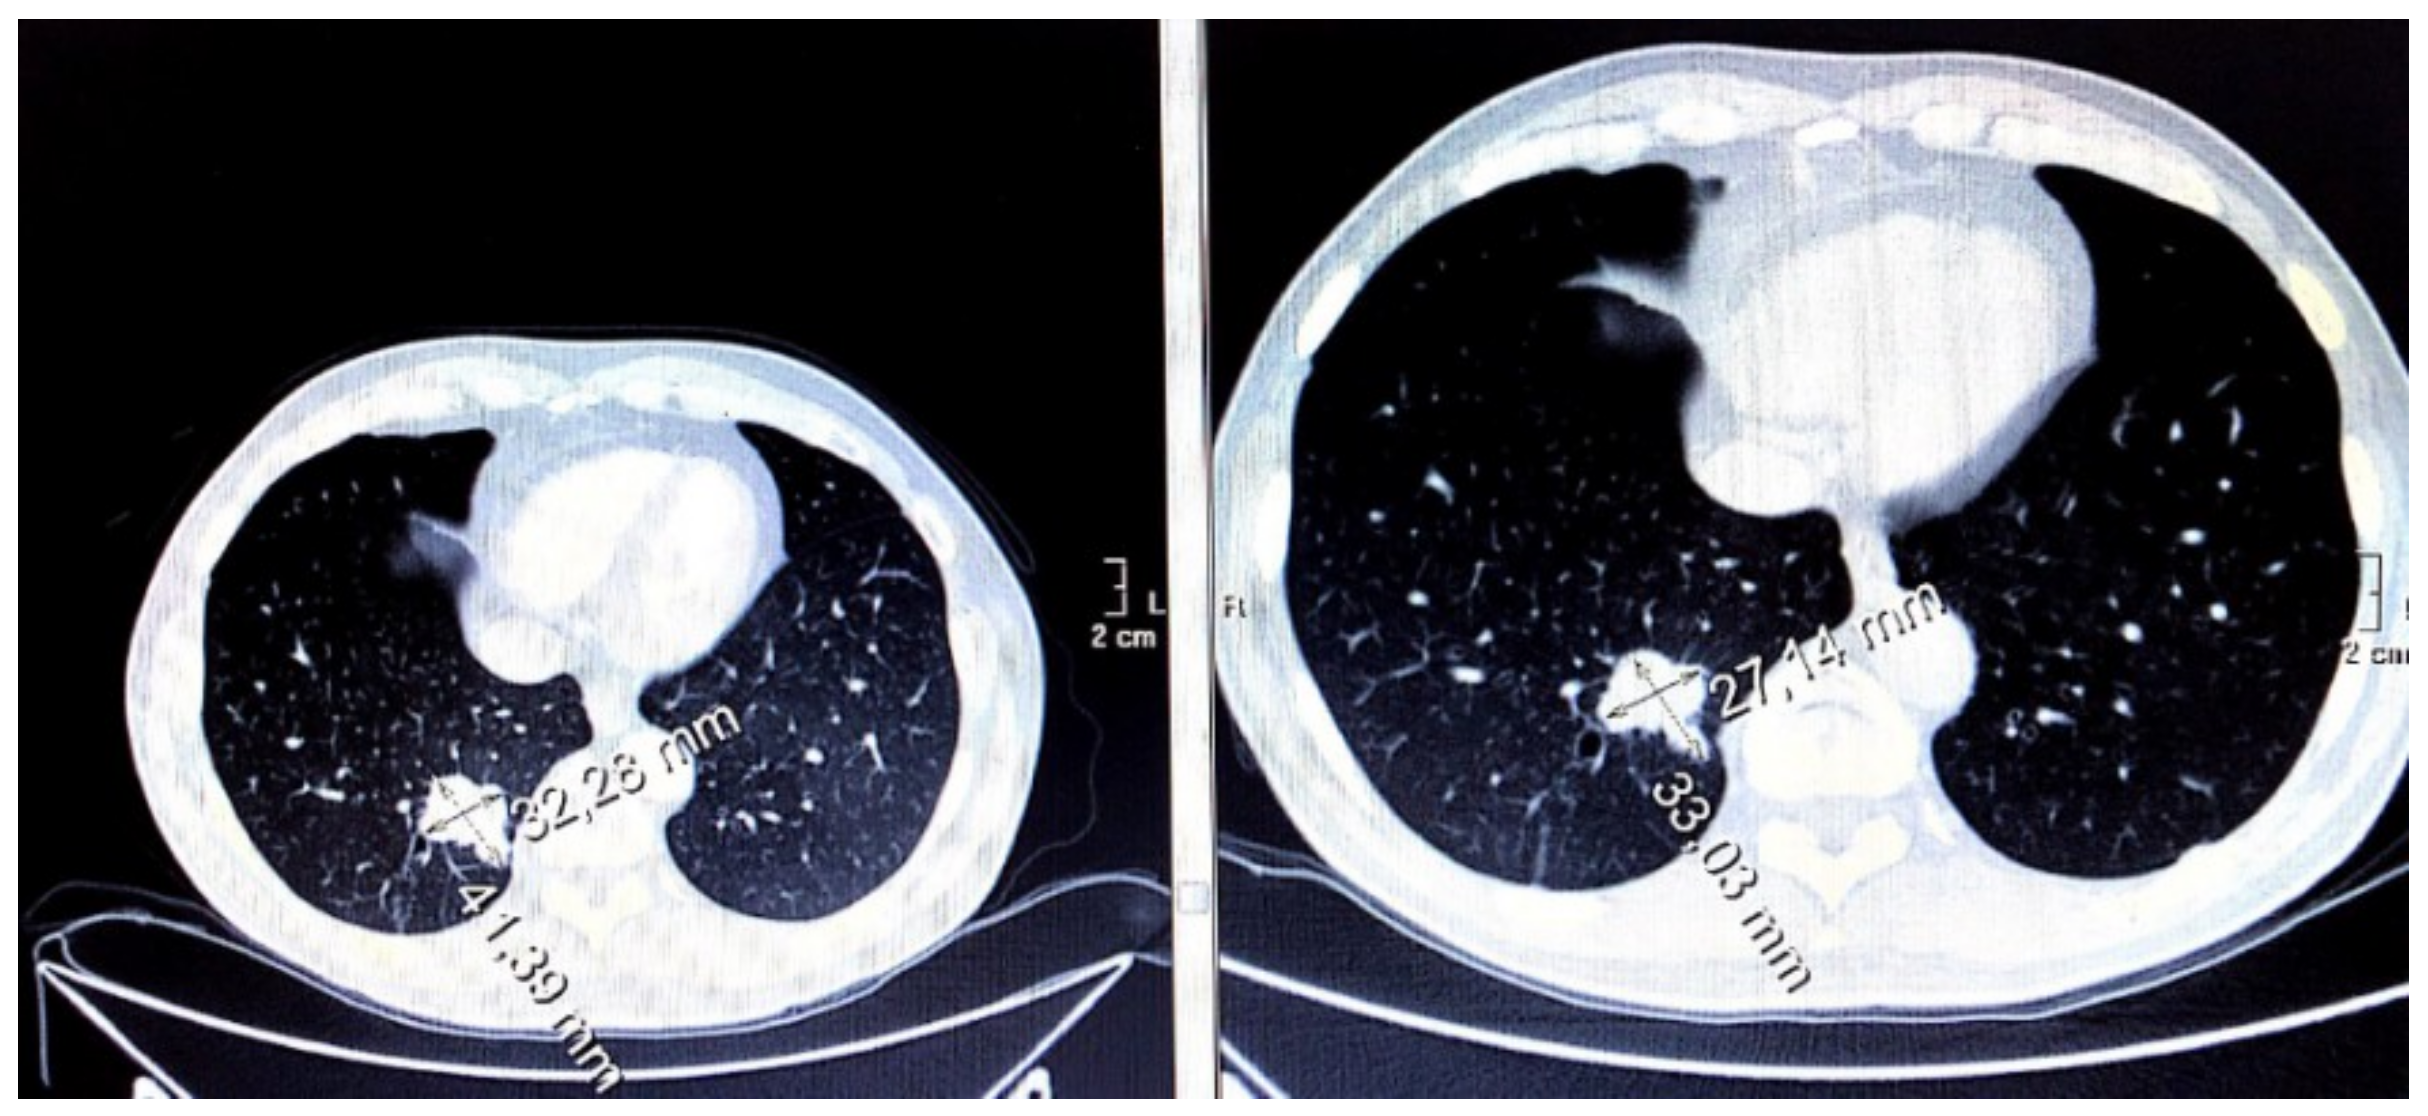

3.7. Evaluation of Disease Wuìith CT Imaging